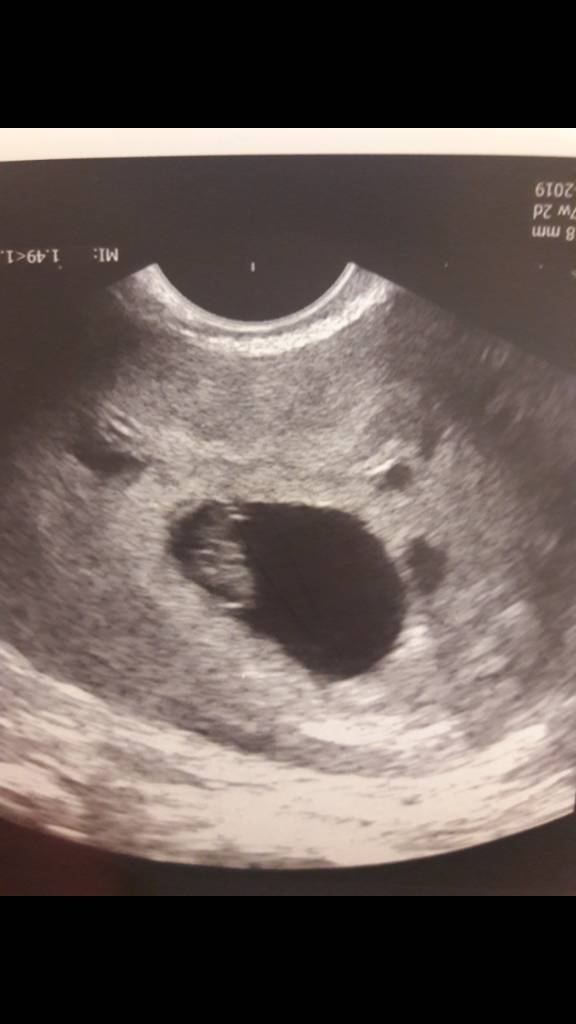

Cześć Dziewczyny, jestem po transferze 2 zarodków (07/07). Martwię się bo beta spadła z 36 na 12 :( a także progesteron spadł na 55. Załamka... 7 lat starań